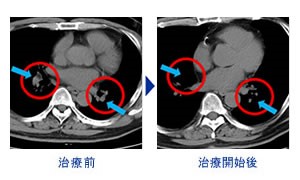

肺癌、 纵隔镜 淋巴结转移(71岁男性)

来院

(抗PD-1抗体)病例

肺癌、 纵隔镜 淋巴结转移(71岁男性)

治疗前摄影图CT (治疗前:CT)

开始治疗后70日后(2个月半)(治疗 70天后)

中国来的患者

来院 PD-1免疫抗癌剂

(抗 PD-1 抗癌剂) 案例

*肺癌, 纵隔镜 淋巴结转移(71 岁男性)

来自中国的一名患者. 1疗程 5回 PD-1免疫抗癌剂(抗PD-1抗癌剂)

并用 免疫疗法NK・T细胞疗法 肿瘤减少了一半以上.

目前.以彻底消除肿瘤为目标.进行第2疗程的治疗.